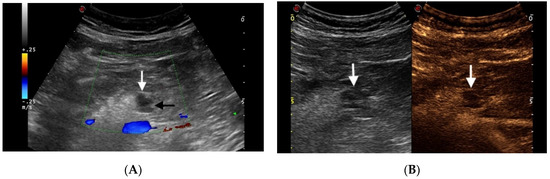

5. Non Neoplastic Cystic Lesions

Pseudocyst